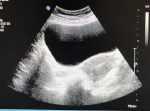

尿頻3年,腰酸半年,腹痛一個月 關(guān)鍵疾病:腹痛 現(xiàn)病史【一般資料】女性,9歲,學(xué)生【主訴】尿頻3年,腰酸半年,腹痛一個月【現(xiàn)病史】3年來患兒無誘因出現(xiàn)尿頻,主要是白天出現(xiàn),夜間不起夜。但無尿急、尿痛,曾經(jīng)多次去診所和醫(yī)院考慮:著涼、尿道感染,經(jīng)過口服消炎藥物和保暖癥狀減輕,但反復(fù)出現(xiàn)一直沒有病愈,后就沒有在意。近半年來出現(xiàn)腰酸,診治于中醫(yī)考慮:腎陰虛,口服中藥癥狀無減輕。腹痛一個月出現(xiàn)腹痛,呈陣發(fā)性,去醫(yī)院考慮:腸痙攣,口服藥物無好轉(zhuǎn)而來診斷。病來無發(fā)熱、飲食及二便正常?!炯韧贰繜o肝炎等傳染病史接觸史。按計劃接種卡介苗、乙肝疫苗、脊髓灰質(zhì)炎疫...

沈*** | 主任醫(yī)師 兒科 小兒內(nèi)科 瀏覽:3849